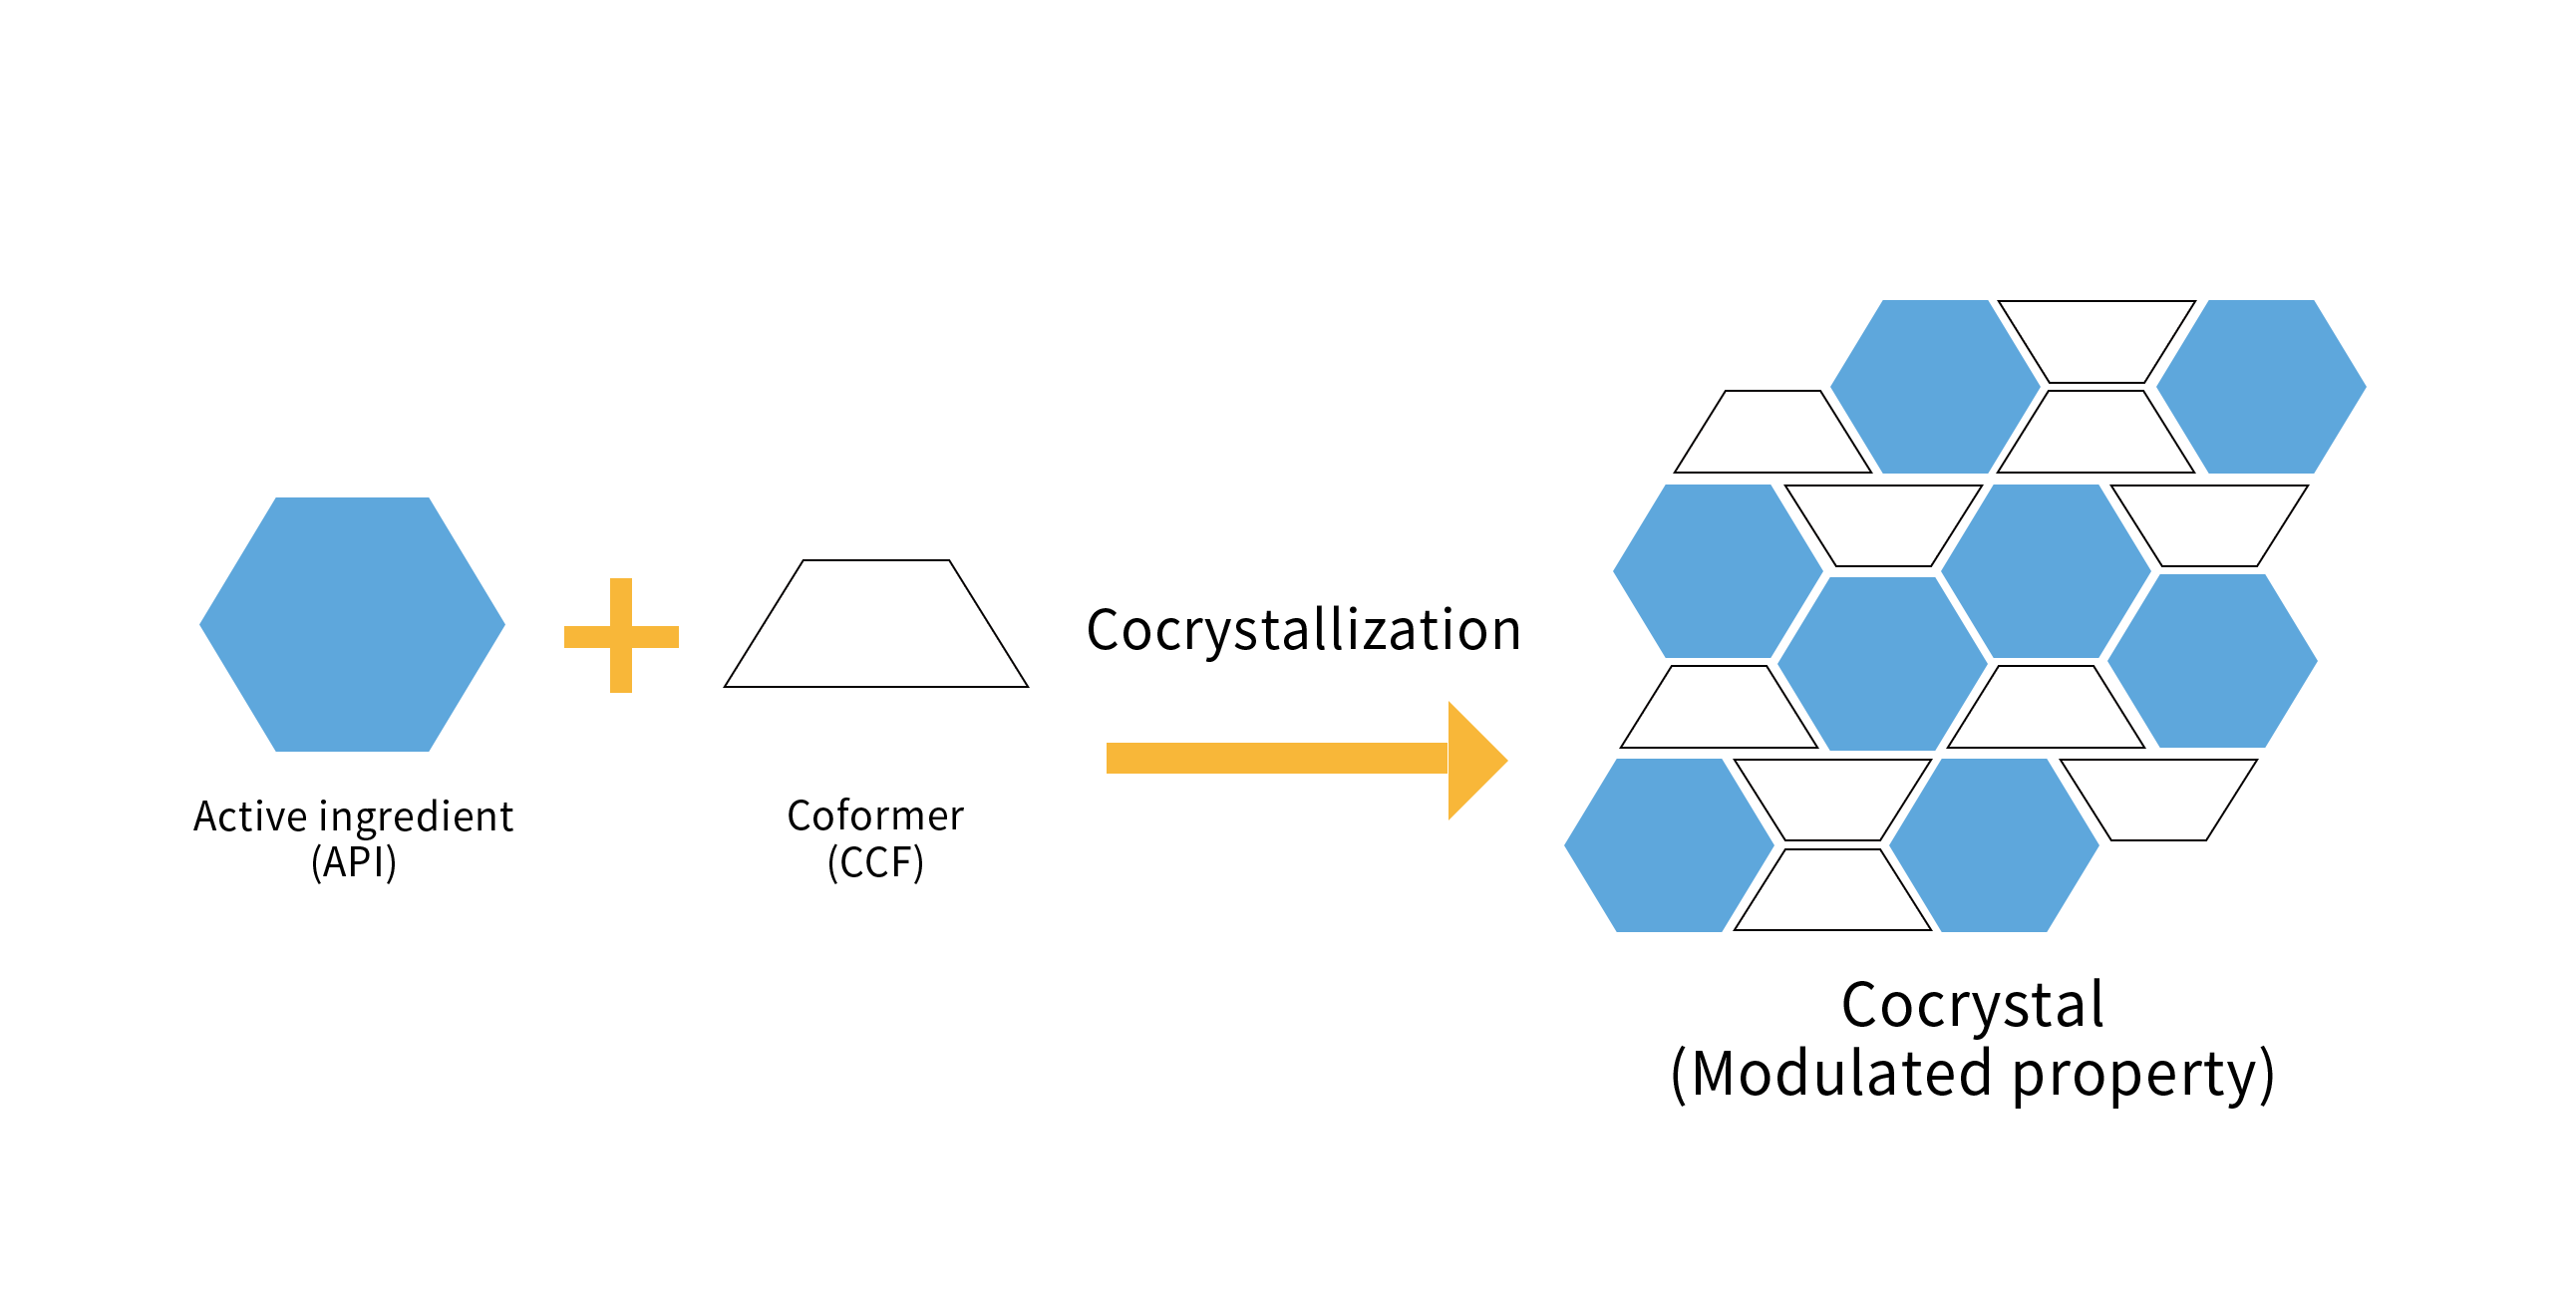

共晶技(jì)術(shù)

共晶技(jì)術(shù)是(shì)有(yǒu)效提高(gāo)活性成分(fēn)溶解度、穩定性和(hé)生(shēng)物(wù)利用(yòng)度的(de)醫Ω(yī)研級分(fēn)子(zǐ)制(zhì)劑技(jì)術(shù)。